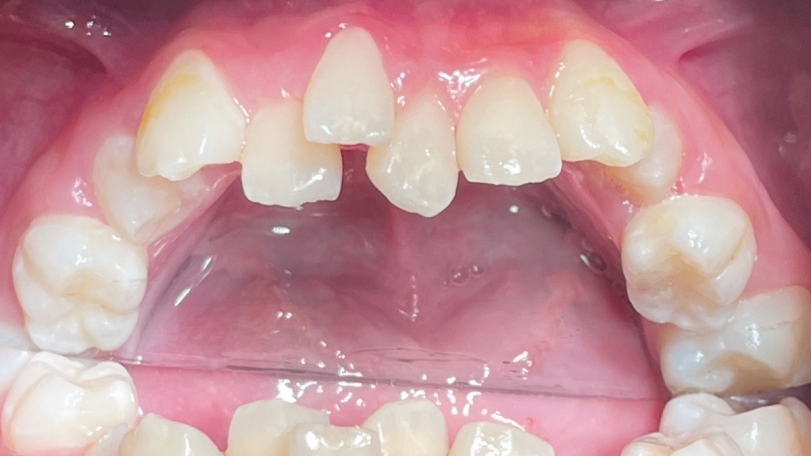

正在換牙期的小茹因齒列先天發育異常,從小就咬合不良,雖然能正常飲食,也不影響說話,但是一口亂牙令她相當困擾,因此在11歲時被媽媽帶來台北慈濟醫院齒顎矯正科評估。全口X光中看到小茹的牙齒不但亂,還有先天缺牙與阻生齒。陳宜宏醫師建議早期進行齒列矯正,也就上述狀況分別處理治療,迄今矯正一年半,先拆除上排矯正器,小茹的齒列與外觀已大幅改善,平整的門牙讓她更有自信,下排牙齒目前持續矯治中。

以小茹為例,經診斷其有:上顎牙弓發育不足、輕微戽斗與門牙排列紊亂、上排雙側犬齒阻生與第二小臼齒先天缺牙、下排雙側第二大臼齒阻生與右下第二小臼齒萌發方向異常。由於狀況複雜,陳宜宏醫師建議以固定矯正器加上顎兩支骨釘為主要治療方式,先針對長不出來的兩顆犬齒做電燒,讓埋在牙齦裡的齒面露出,黏上矯正器;接著拔掉兩顆上顎第二乳臼齒與打上骨釘,利用其將第一小臼齒與犬齒向後拉,同時上門齒慢慢排列整齊,考量小茹上顎先天缺牙且上下牙齒顆數必須對稱,故拔除下顎兩顆第一小臼齒來獲得空間,並將下門牙排列整齊。